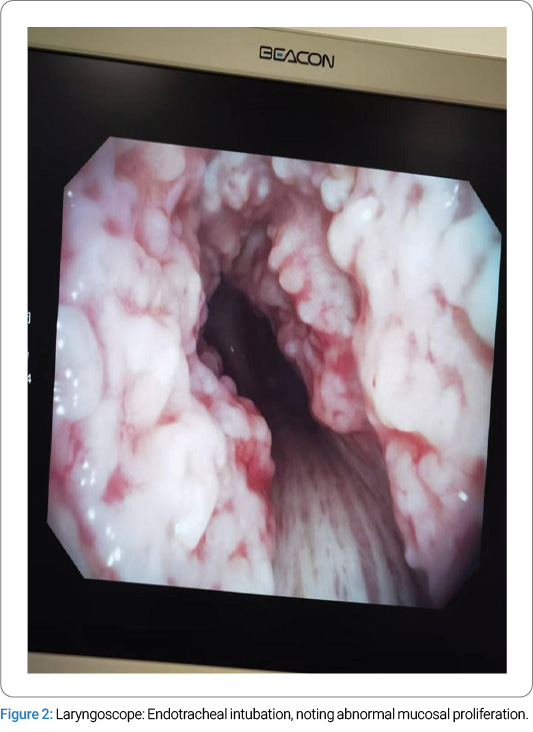

Diagnostic and Therapeutic Process:Following admission, preoperative preparations were promptly completed. On January 14, 2025, the patient was scheduled for a laparoscopic cholecystectomy under general anesthesia with endotracheal intubation. Routine anesthetic induction was administered with sufentanil 50 μg, midazolam 2 mg, etomidate 12 mg, and rocuronium 50 mg. After an adequate anesthetic effect was achieved, a video laryngoscope was inserted for endotracheal intubation, during which abnormal mucosal proliferation was noted in the trachea below the glottis (Figure 2). A senior anesthesiologist was consulted, and a visual stylet was utilized, revealing extensive proliferation distal to the glottis. A review of the chest CT demonstrated intraluminal protruding calcifications (Figure 1). Mask ventilation was maintained, and neuromuscular blockade was reversed. Following the patient’s full recovery of consciousness, the attending physician informed the patient’s family of the need for further investigations to clarify the airway pathology. The surgery was canceled, and the patient was transferred back to the ward. Subsequent flexible laryngoscopy and bronchoscopy revealed irregular exophytic lesions involving the trachea from the subglottic regionto the carina, accompanied by tracheal stenosis. Multiple scattered nodular changes were observed in the airway, with severe stenosis in the lower tracheal segment precluding bronchoscopic passage. Three biopsy specimens were obtained from the upper and middle tracheal segments and submitted for pathological examination. Pathological diagnosis: Chronic inflammatory cell infiltration of the mucosa, with squamous metaplasia and abundant calcified deposits.